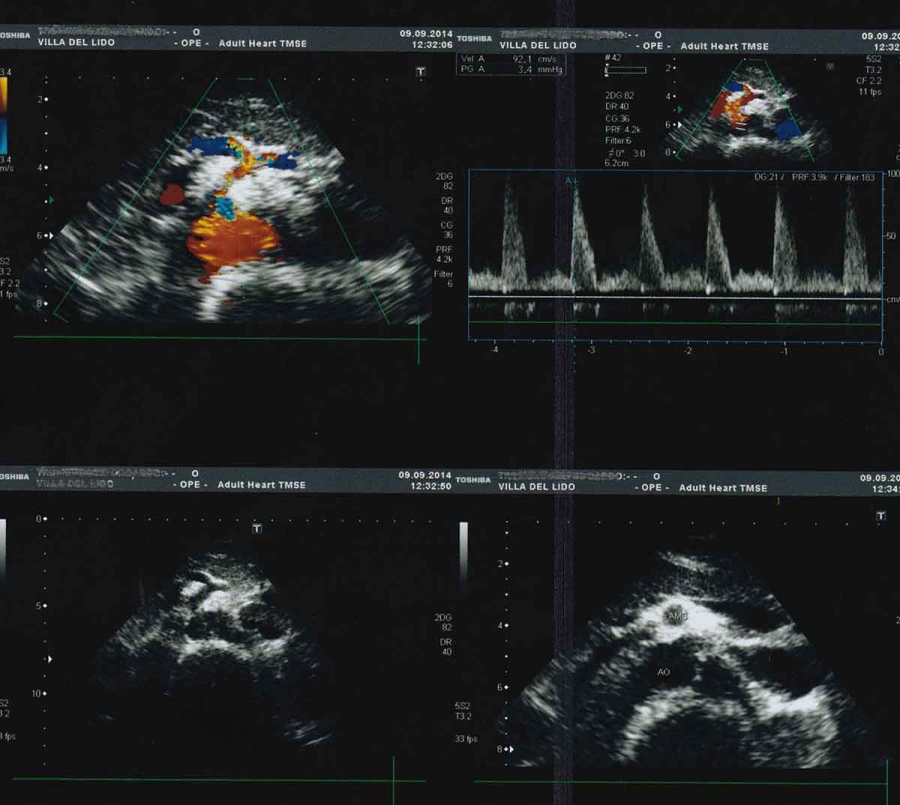

Ecocolordoppler dell’aorta addominale

L’esame ecografico dell’aorta addominale ha principalmente lo scopo di identificare per tempo la dilatazione ( aneurisma ) di questa grossa arteria. L’esame consiste nell’appoggiare una sonda ecografica sull’addome, da sotto lo sterno fino all’ombelico, e nella registrazione delle immagini e dei grafici doppler.